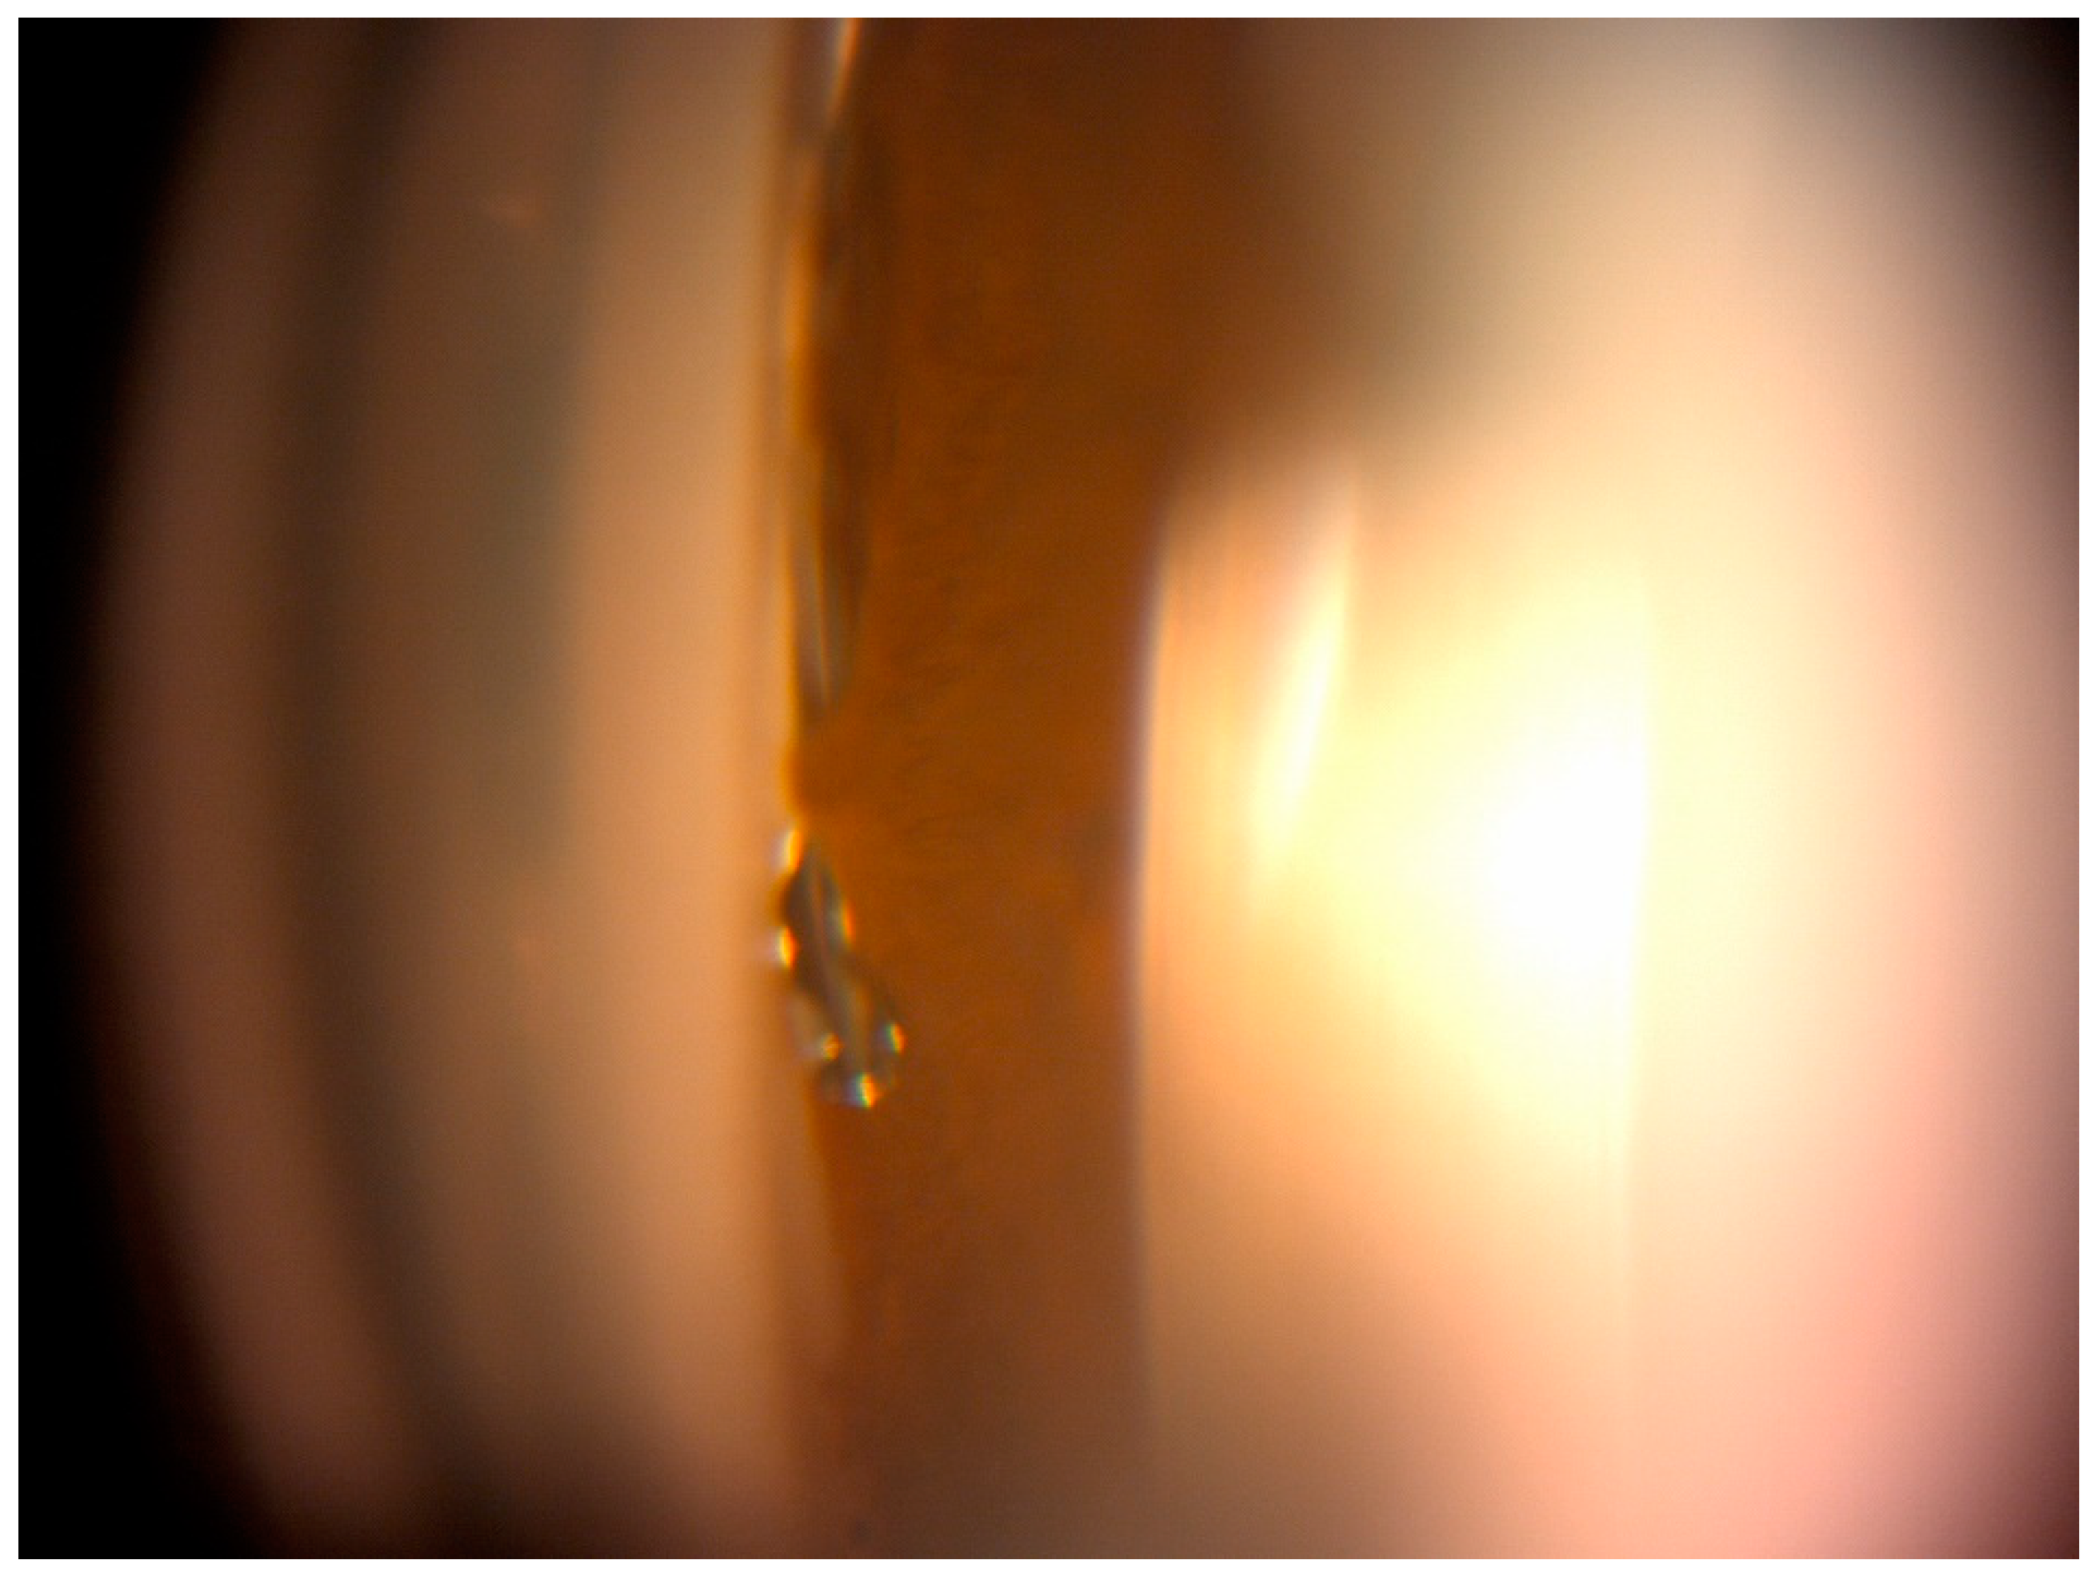

Results were collected during follow-up visits performed as follows: at 1 day, 7 days (±2 day), 1 month (±7 days), 3 months (±14 days), 6 months (±21 days), 12 months (±30 days), 18 months (±42 days), 24 months (±60 days), and 30 months (±60 days). Preoperative examination included obtaining patient data (age, sex, antiglaucoma medications, and surgery procedures). Basic procedures included IOP measurement using a Goldman applanation tonometer, best-corrected visual acuity (BCVA) using the Snellen chart, anterior segment assessment with funduscopic examination using a slit lamp, and Goldmann three-mirror lens for gonioscopy assessed with Schaffer classification. Postoperatively, BCVA, IOP, and number of antiglaucoma medications were assessed, and the anterior segment and fundus were examined at each control visit. Postoperative complications included hypotony (defined as an IOP < 6 mmHg), microhyphema, keratitis, peripheral anterior synechiae (PAS) (Figure 1), device migration or dislocation. All antiglaucoma medications were withdrawn after the surgery. When the target IOP was not achieved after surgery it was re-administrated according to the EGS guidelines [3]. After surgery, all patients were prescribed antibiotic and anti-inflammatory eye drops for 4 weeks.

Figure 1.

Gonioscopic view of Hydrus microstent showing peripheral anterior synechiae.

3.4. Safety

Significant observation due to the frequency of occurrence was a transient increase in IOP ≥ 10 mmHg from baseline. This complication was noted in 6.7% of cases in the Hydrus group and in 11.4% in the iStent group. The odds of this happening in our study were 1.8 times greater for the iStent group than for the Hydrus group. In the literature, IOP increases are also higher for the iStent implant (from 1.1% to 21%) than for the Hydrus implant (from 4.76% to 6.5%) [14,19]. In our observations, the adverse event characteristic of the Hydrus group was the formation of PAS. We noted PAS in 20% of operated eyes in this group. The developed peripheral synechiae occurred as focal adhesion of the iris to the implant and were located near its inlet (Figure 1). The presence of PAS did not cause implant occlusion in any of the cases. In the works of other authors, PAS appears equally often in 14.9% of the Horizon Study [17], in 19% of Pfeiffer’s [26] and in 19% of Gandolfi [16]. In cases where the PAS is located at the inlet of the stent, obstruction is possible, as noted in a small percentage of cases by Pfeiffer and Samuelson in the Horizon Study [17,26]. Iris adherence followed by implant obstruction is reported in some iStent observations (3–4.3%) [9,12], but is much less frequent than PAS in the Hydrus implant, which may be related to the size of the stent. The small size of the iStent may also explain the cases of migration (2.6%) [12]. Despite the small size of the study groups, we observed hypotony, which is rare in MIGS procedures. This was in one case in the Hydrus group. Hypotony developed on the 7th day after surgery and spontaneously resolved within 1 week without the need for additional interventions. Transient hypotony was described by Samuelson in the case of the iStent [9]. As in our observation, this case did not require additional therapeutic measures. Risk of postoperative hypotension for SC-implanted stents is low because the lowest IOP achievable by bypassing the trabeculum is a few mmHg higher than the EVP.